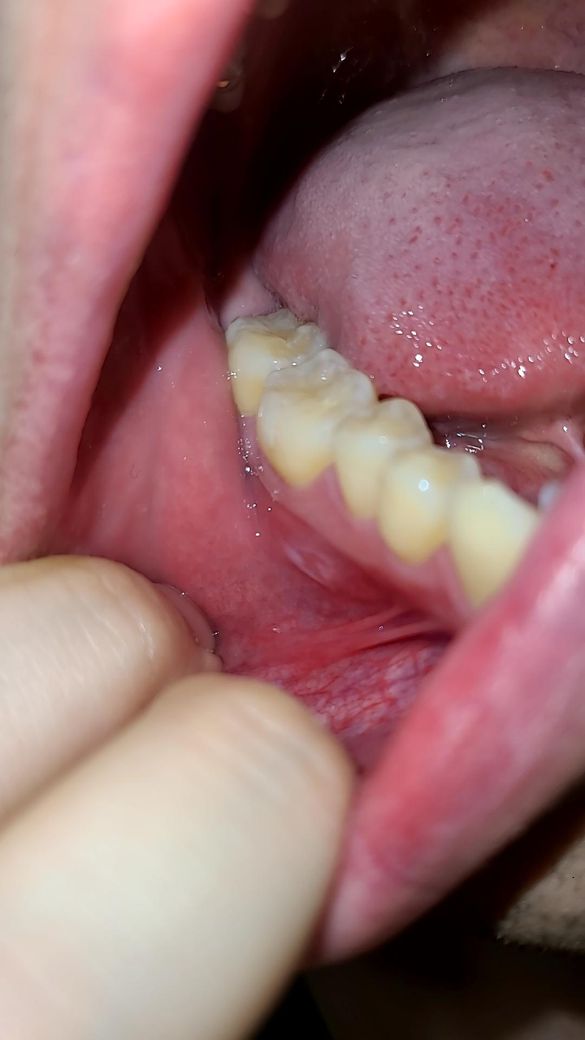

구내염 인지 뭔가가 좀 오래지속되는데요 구강암인가요

1주 더지나서 오늘 보니까 하얀게 보이네요

불편한건 더 심해졌어요

• 3번 째 사진

악성병소보다는 구내염에 가까운 것으로 사진상 보이는데요

오라메디 적용해보시고 호전되지 않으면 구강내과 가보세요